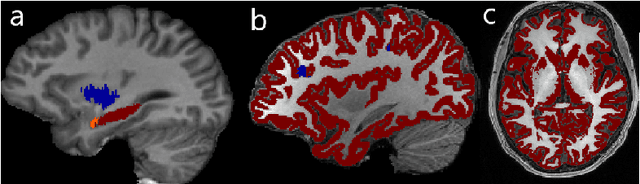

Abstract:In applications of supervised learning applied to medical image segmentation, the need for large amounts of labeled data typically goes unquestioned. In particular, in the case of brain anatomy segmentation, hundreds or thousands of weakly-labeled volumes are often used as training data. In this paper, we first observe that for many brain structures, a small number of training examples, (n=9), weakly labeled using Freesurfer 6.0, plus simple data augmentation, suffice as training data to achieve high performance, achieving an overall mean Dice coefficient of $0.84 \pm 0.12$ compared to Freesurfer over 28 brain structures in T1-weighted images of $\approx 4000$ 9-10 year-olds from the Adolescent Brain Cognitive Development study. We then examine two varieties of heteroscedastic network as a method for improving classification results. An existing proposal by Kendall and Gal, which uses Monte-Carlo inference to learn to predict the variance of each prediction, yields an overall mean Dice of $0.85 \pm 0.14$ and showed statistically significant improvements over 25 brain structures. Meanwhile a novel heteroscedastic network which directly learns the probability that an example has been mislabeled yielded an overall mean Dice of $0.87 \pm 0.11$ and showed statistically significant improvements over all but one of the brain structures considered. The loss function associated to this network can be interpreted as performing a form of learned label smoothing, where labels are only smoothed where they are judged to be uncertain.